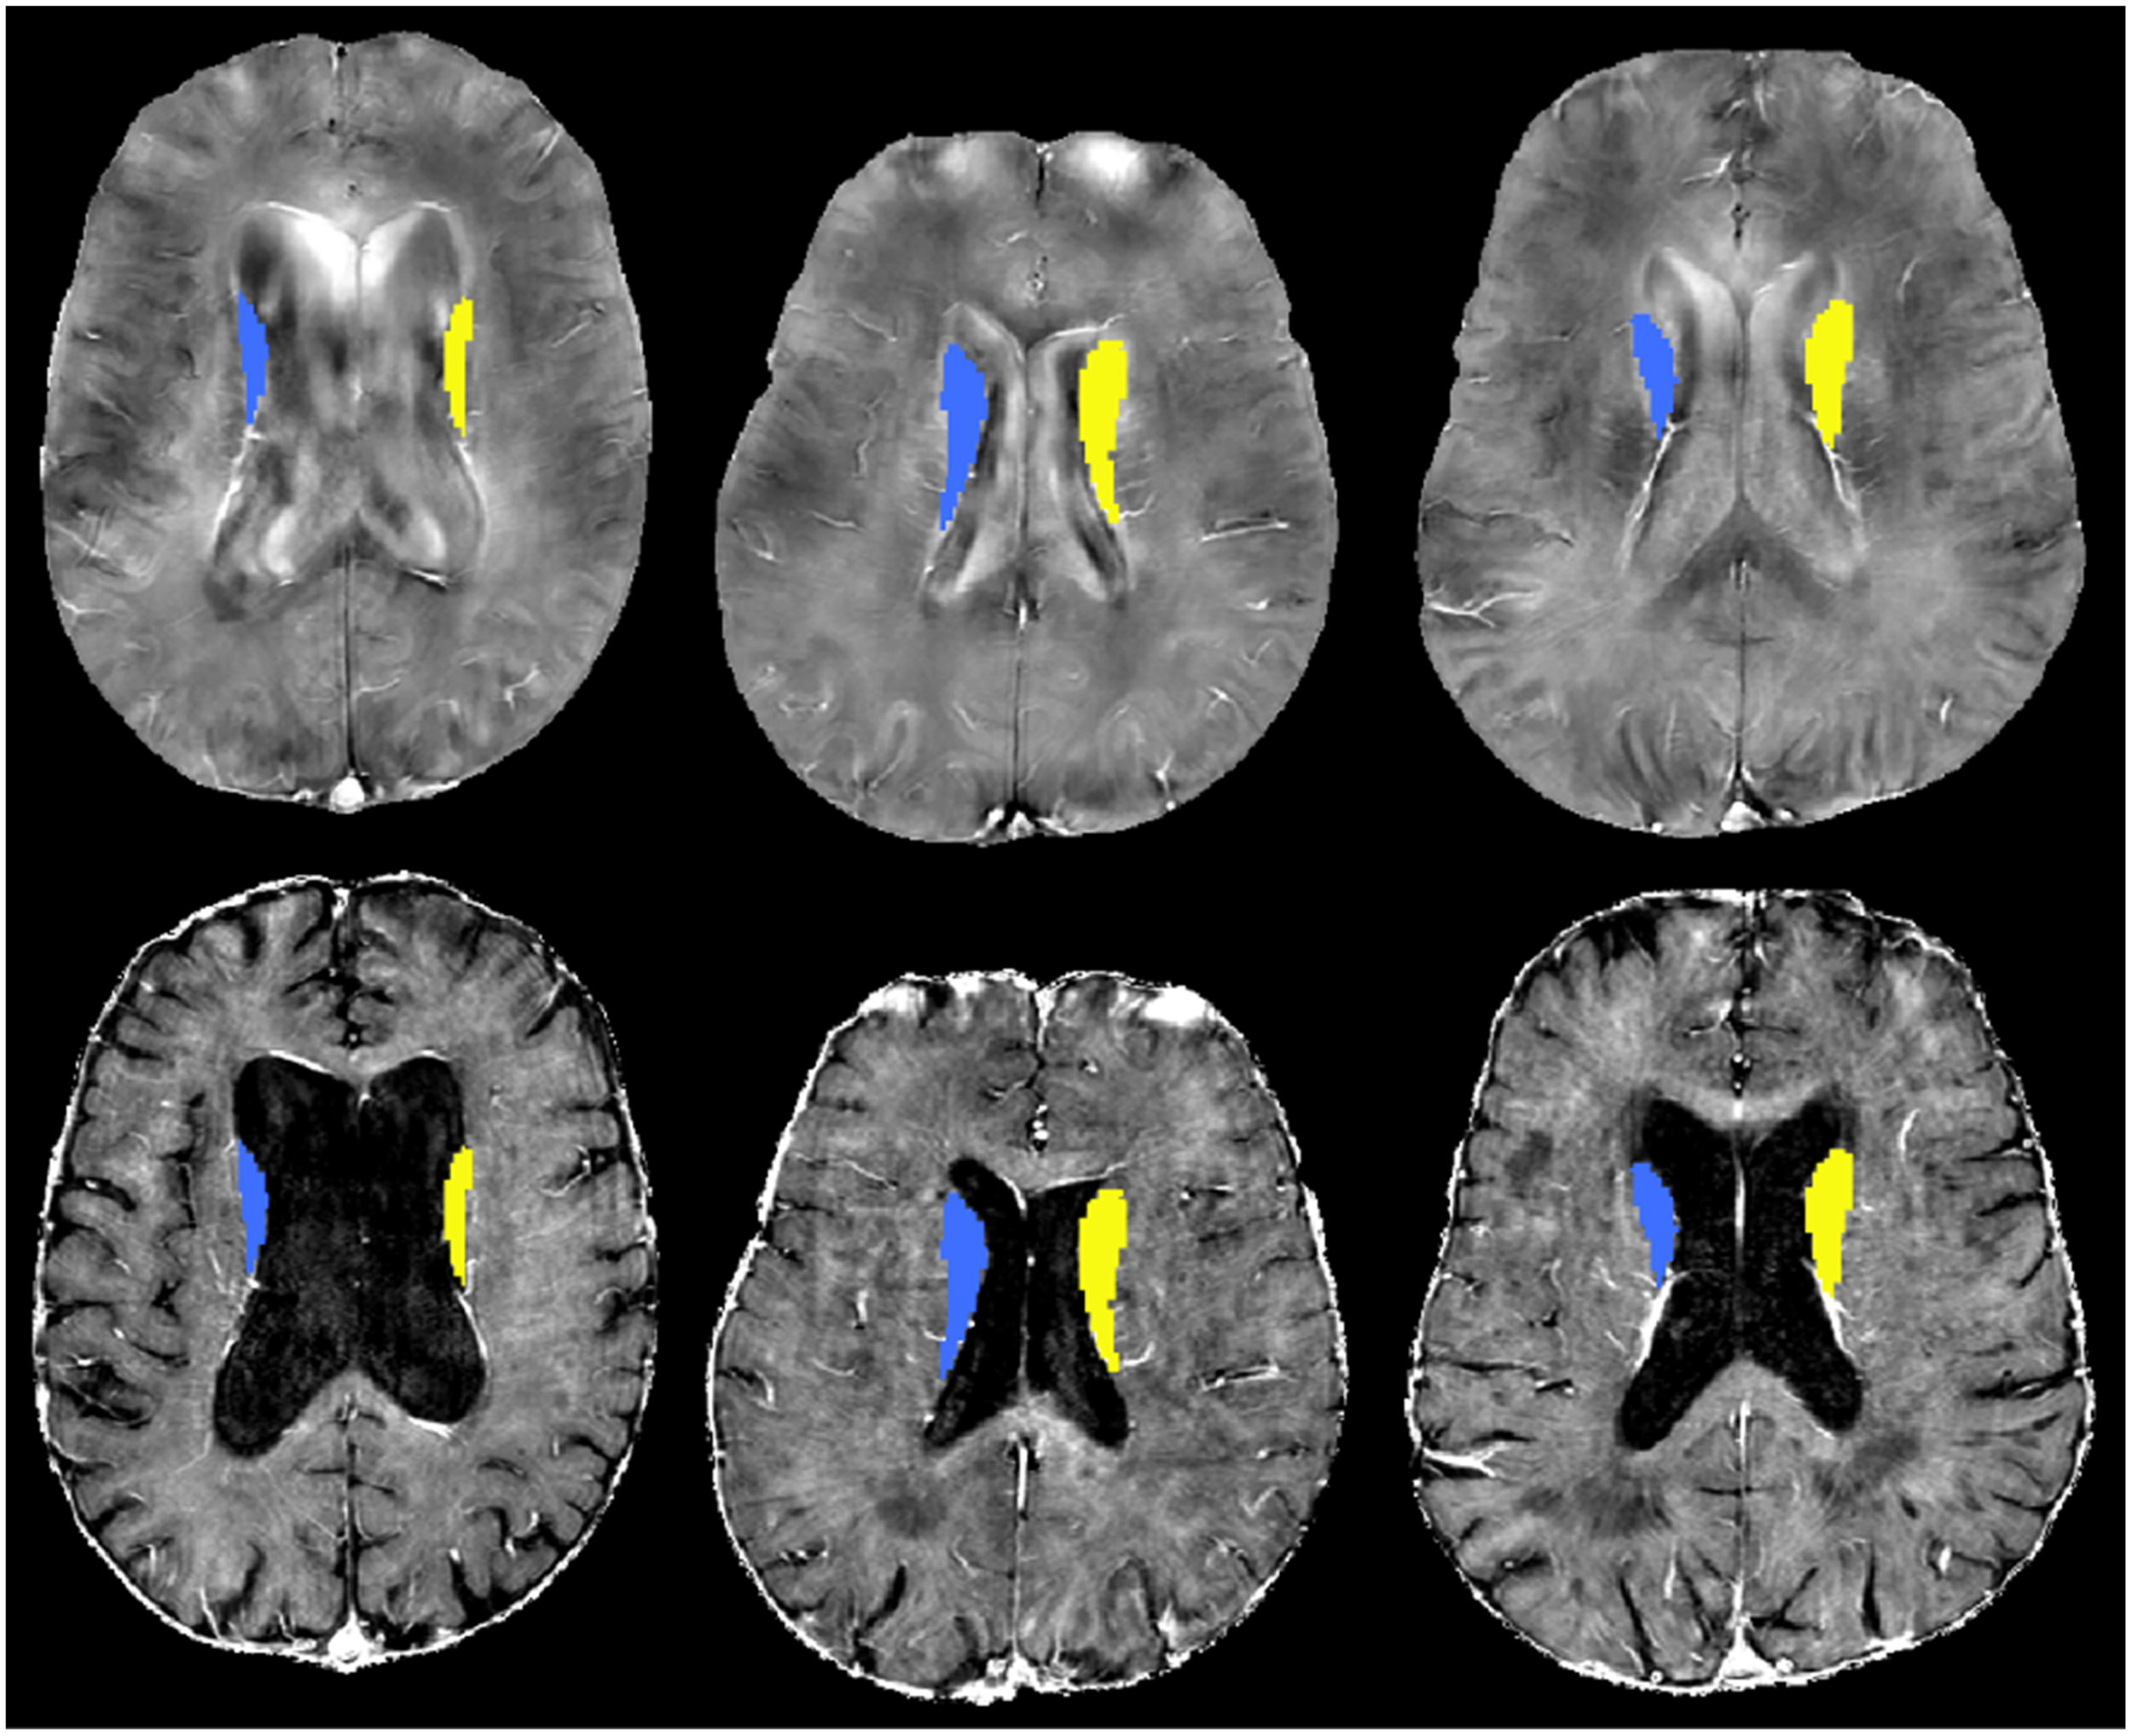

Un aumento de cuatro o cinco puntos en el índice de masa corporal se asocia con un incremento de entre el 50% y el 90% del riesgo de demencia vascular, según distintos análisis genéticos, un resultado consistente en varias poblaciones y métodos estadísticos. Cortesía: Lee H, Wiggermann V, Rauscher A, et al. / Canadian Journal of Neurological Sciences